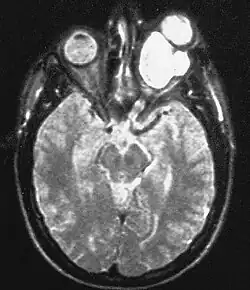

Glejak nerwu wzrokowego

Glejak nerwu wzrokowego (ang. optic nerve glioma) – kliniczne określenie nowotworów złośliwych przedniego odcinka drogi wzrokowej, najczęściej są to gwiaździaki włosowatokomórkowe (gąbczaki). Rzadziej są to glejaki włókienkowe, zwojakoglejaki i glejaki nisko zróżnicowane. Są to rzadkie nowotwory, stanowią 1-1,7% glejaków. Są częstsze u dzieci (90% występuje poniżej 20. roku życia); stanowią 3-5% wewnątrzczaszkowych guzów u dzieci[1]. W ponad 50% glejak nerwu wzrokowego współistnieje z nerwiakowłókniakowatością typu I (chorobą von Recklinghausena), stanowiąc jedno z kryteriów rozpoznania tego schorzenia.